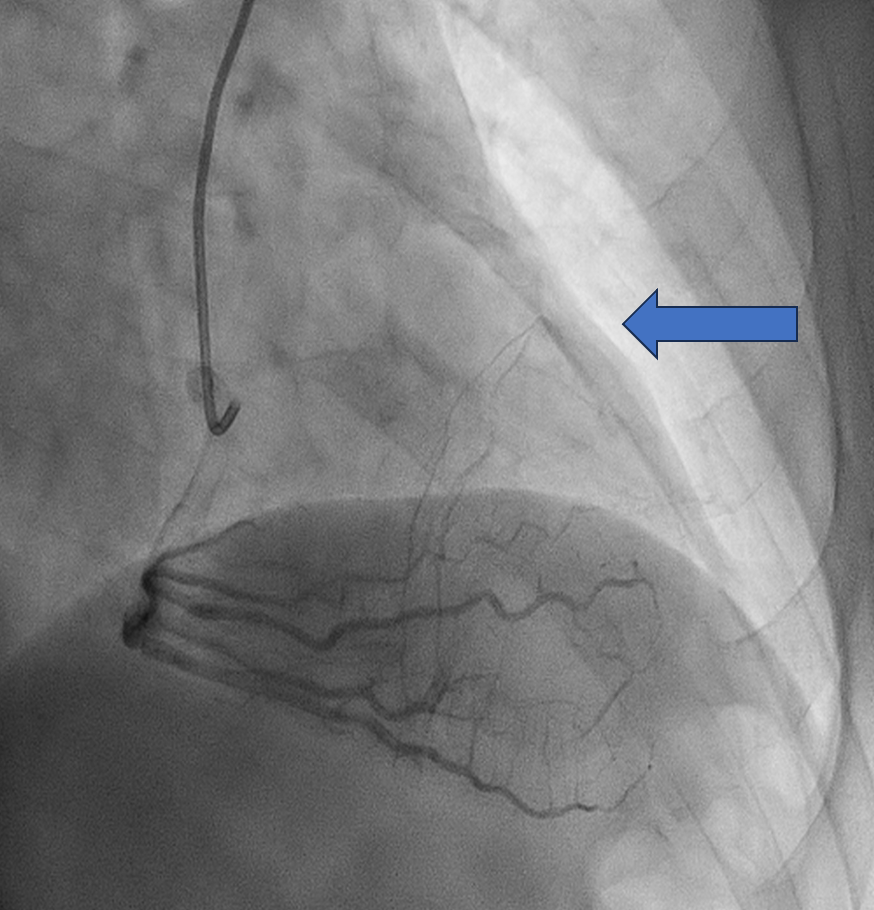

WE DECIDED TO INTERVENE THE CTO MLAD IN VIEW PERSISTENT ANGINA. BILATERAL RADIAL ARTERY PUNCTURE, WITH ANTEGRADE APPROACH. WE ENGAGED RIGHT CORONARY ARTERY WITH JR4 6 FR AND WIRED DOWN WITH RUNTHROUGH FLOPPY. ENGAGED THE LEFT CORONARY ARTERY WITH EBU 3.5 7FR. INITIALLY TRIED TO WIRE THE LAD WITH FINECROSS MICROCATHER (MC) USING SION BLACK WIRE BUT FAILED. SUBSEQUENTLY CHANGED TO GAIA 1ST AND MANAGED TO CROSS SUCCESSFULLY. IVUS SHOWED 360 DEGREE CALCIFICATION WITH 270 DEGREE CALCIFICATION MORE THAN 5 MM, IVUS CALCIUM SCORE 2. CALCIUM DEBULKING WAS DONE USING ROTABLATION WITH 1.5 BURR RUN 3 TIMES AT 220 KRPM FOR 10 SECS AND POLISHING RUN TWICE AT 140 KRPM. POST ROTA SHOWED PRESENCE OF FRACTURED CALCIUM WITH REVEBERATION SIGN. LESIONS WAS PREPARED FURTHER USING WOLVERINE 3.0 X 10MM AND 3.5 X 10MM. POST CUTTING BALLOON SHOT SHOWED NO DISSECTION, TIMI 3 FLOW AND RESIDUAL STENOSIS 30%. DECIDED FOR DCB WITH PANTERA LUX 3.0 X 20MM AND AGENT 3.50 X 30MM. FINAL SHOT SHOWED TIMI3 FLOW, NO DISSECTION SEEN. PATIENT REMAIN ASYMPTOMATIC AT 6 MONTHS AND REPEATED COROS SHOWED MODERATE STENOSIS AT MLAD WITH NEGATIVE FFR (0.92).

Case Summary